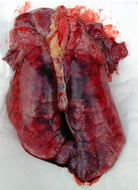

Nous avons fait sur place l'autopsie d'1 porcelet âgé de 2 mois choisi parmi ceux de la salle 5 (amaigri et avec un " coup de flanc ") :

Les lésions observables sont situées au niveau de la cavité thoracique :

*

Congestion généralisée et pneumonie touchant partiellement

tous les lobes (Note 10/28) * Léger œdème interlobulaire * Pleurésie surtout sur les lobes diaphragmatiques * Légère péricardite avec adhérence du péricarde |